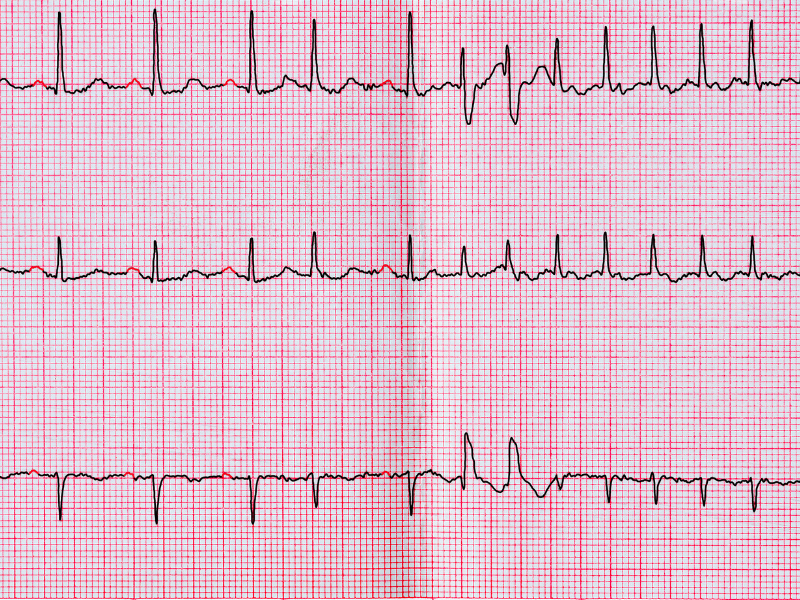

Figura 2: Ritmo sinusal alternando com ritmo de fibrilação atrial. A análise do ritmo é a segunda etapa na interpretação dos achados do traçado.

Figura 2: Ritmo sinusal alternando com ritmo de fibrilação atrial. A análise do ritmo é a segunda etapa na interpretação dos achados do traçado.

Já os ritmos irregulares são aqueles em que o intervalo RR é variável a cada batimento. Sem dúvida, o principal representante desse tipo de ritmo é a fibrilação atrial, que também apresenta como elemento para o diagnóstico a ausência da onda P e, eventualmente, a percepção de ondas f (minúscula) que indicam a ativação caótica dos átrios nesta arritmia. Outros ritmos irregulares que podemos encontrar são o flutter atrial, as taquicardias atriais com condução AV variável e eventualmente alguns tipos de taquicardias ventriculares.

Tabela 1: A composição do acrônimo FRABESBI³ Figura 2: Ritmo sinusal alternando com ritmo de fibrilação atrial. A análise do ritmo é a segunda etapa na interpretação dos achados do traçado.

Figura 2: Ritmo sinusal alternando com ritmo de fibrilação atrial. A análise do ritmo é a segunda etapa na interpretação dos achados do traçado. Figura 3: A avaliação do átrio ocorre principalmente observando a onda P nas derivações DII e V1.